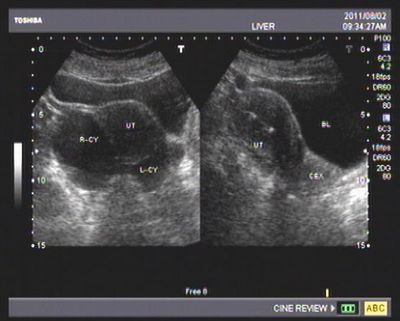

卵巢癌b超图片

卵巢癌的早期症状b超图片